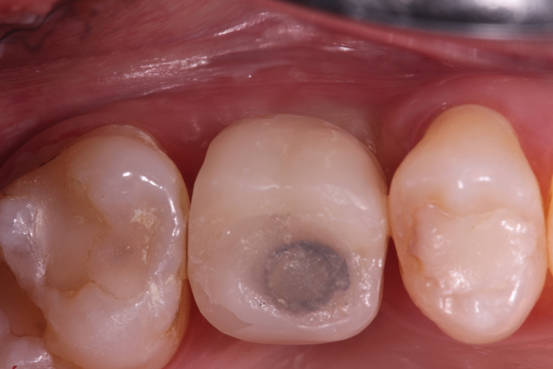

Enfim, um implante osseointegrável de 5.0 x 10 mm TS III (Osstem, Seul, República da Coréia) foi instalado (Figura 14). Após três meses foi feita a reabertura com enxerto de tecido conjuntivo do palato na vestibular e instalação de um cicatrizador (Figura 15). Um mês depois, um provisório foi instalado para promover o correto perfil de emergência gengival (Figura 16) e, então, foi utilizado um corpo de escaneamento (Osstem, Seul, República da Coréia), conforme Figura 16, para a realização do escaneamento para a moldagem digital. Uma coroa em dissilicato de lítio sobre pilar de titânio “Rigid” (Osstem, Seul, República da Coréia) foi confeccionada e parafusada sobre o implante com torque de 30 Ncm (Figura 17). Uma radiografia periapical final sugere a osseointegração do implante, a estabilidade do enxerto ósseo na região do seio maxilar e a perfeita adaptação protética após 12 meses (Figura 18).